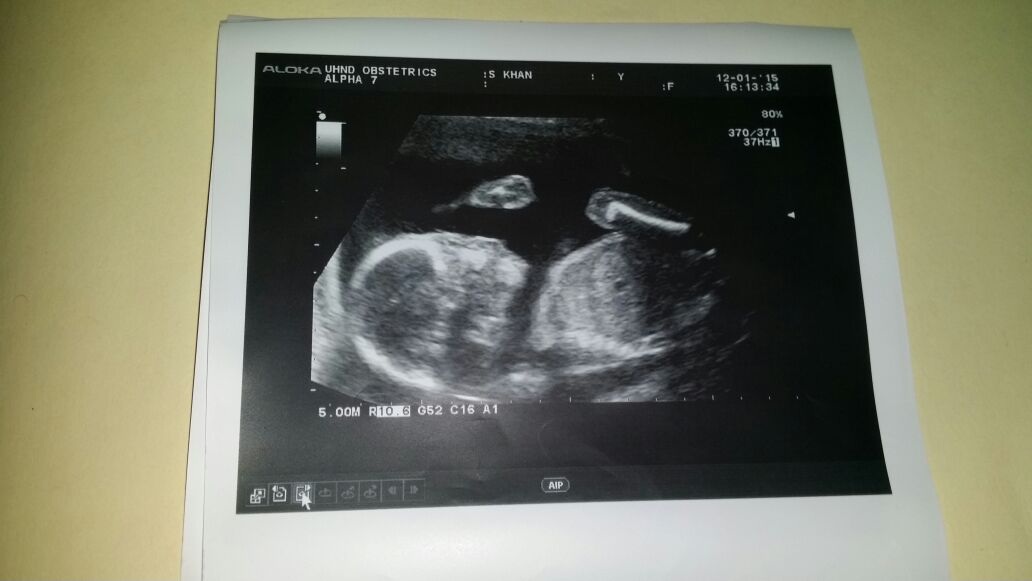

Any guesses folks?? at the moment I have no clue at all, one of the photos dosent even make sense.......

I have no idea regarding nub as it's not applicable for your pic so I'ma gonna use the skull theory which is even less accurate and go with boy.

Looks like your little bean likes lifting their hands above their head and going for the chilling out pose. Cute!

no gender clues arms in the second one are the same as the first but the whole arm wasnt imaged and the second one is the leg bent high up and that is the leg bone. Baby is definitely chilling out in there :)

Sorry for the delayed update folks but i thought i still mention it...."He" is 2 years old now :)